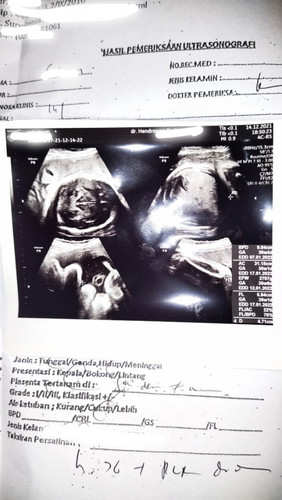

KU KIRA CIRI JANIN MASUK PANGGUL, TERNYATA PLACENTA PREVIA

serius nanya bun,ada ga di sni yg punya pengalaman sama kyk aku?dan bisa lahir normal/ sesar ya bun? Jadi aku tiap bulan USG selama ini normal² aja,tp pas di usia kandungan 36 week kata dokternya placenta menutupi jalan lahir(placenta previa)auto kepikiran bun,krna katanya bs jd nanti harus sesar,pdhl selama ini aku ga ngalamin gejala² placenta previa,spt pendarahan dll. Cuma emg d trimester ke 3 ini kdang perut suka kenceng dan slengki kdang nyeri kirain itu ciri msuk panggul😭 sharing dong bun pengalaman nyaaa#seriusnanya #bantusharing #ingintahu